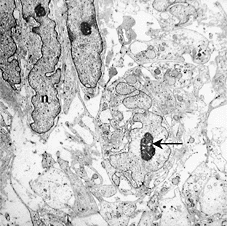

線維肉腫(低分化型)の電子顕微鏡像は紡錘形ないし一部類円形化した腫瘍細胞の増殖を示している。核は核縁の切れ込みが目立ち、明瞭な核小体を有している(図3矢印)。核クロマチンは核内(n)に均等に分布しており、細胞間には膠原線維が認められる(図4)。細胞膜は部分的に突起を示し、細胞内には一部、不規則に拡張した豊富な粗面小胞体がみられる。この粗面小胞体には無構造ないしは顆粒状物質を入れている。

図3 線維肉腫の電顕像 4000倍 図4 線維肉腫の電顕像 4800倍 図5 線維肉腫の電顕像 4800倍